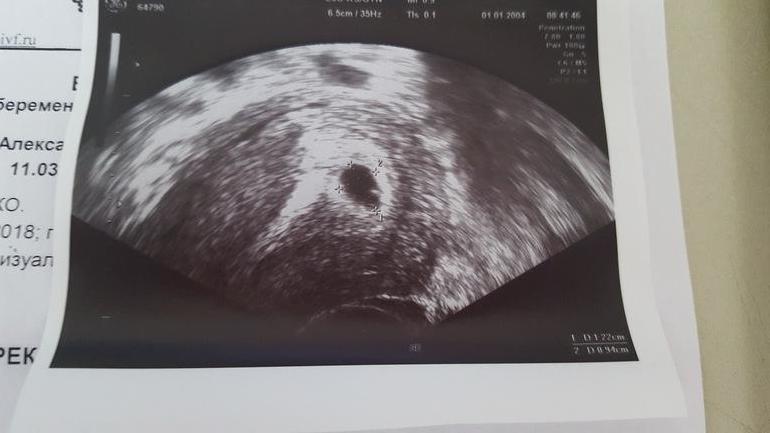

Вчера приехала к Ре на УЗИ и она мне показала мою крошку😊 Плодное яйцо 12 мм и в нем маленькая крохотуличка. Даже удалось уловить сердцебиение❤❤❤

23 дпп. Пункция была 30.03, а перенос 4.04. Ре сказала, что цель первого УЗИ увидеть ПЯ и убедиться, что оно в матке, исключив вариант внематочной беременности.

Перед УЗИ настраивала себя, что на этом сроке могут не увидеть эмбриончик и сб. Но судя по всему мне повезло. Правда малыш за время УЗИ несколько раз прятался и пропадал из виду.)))